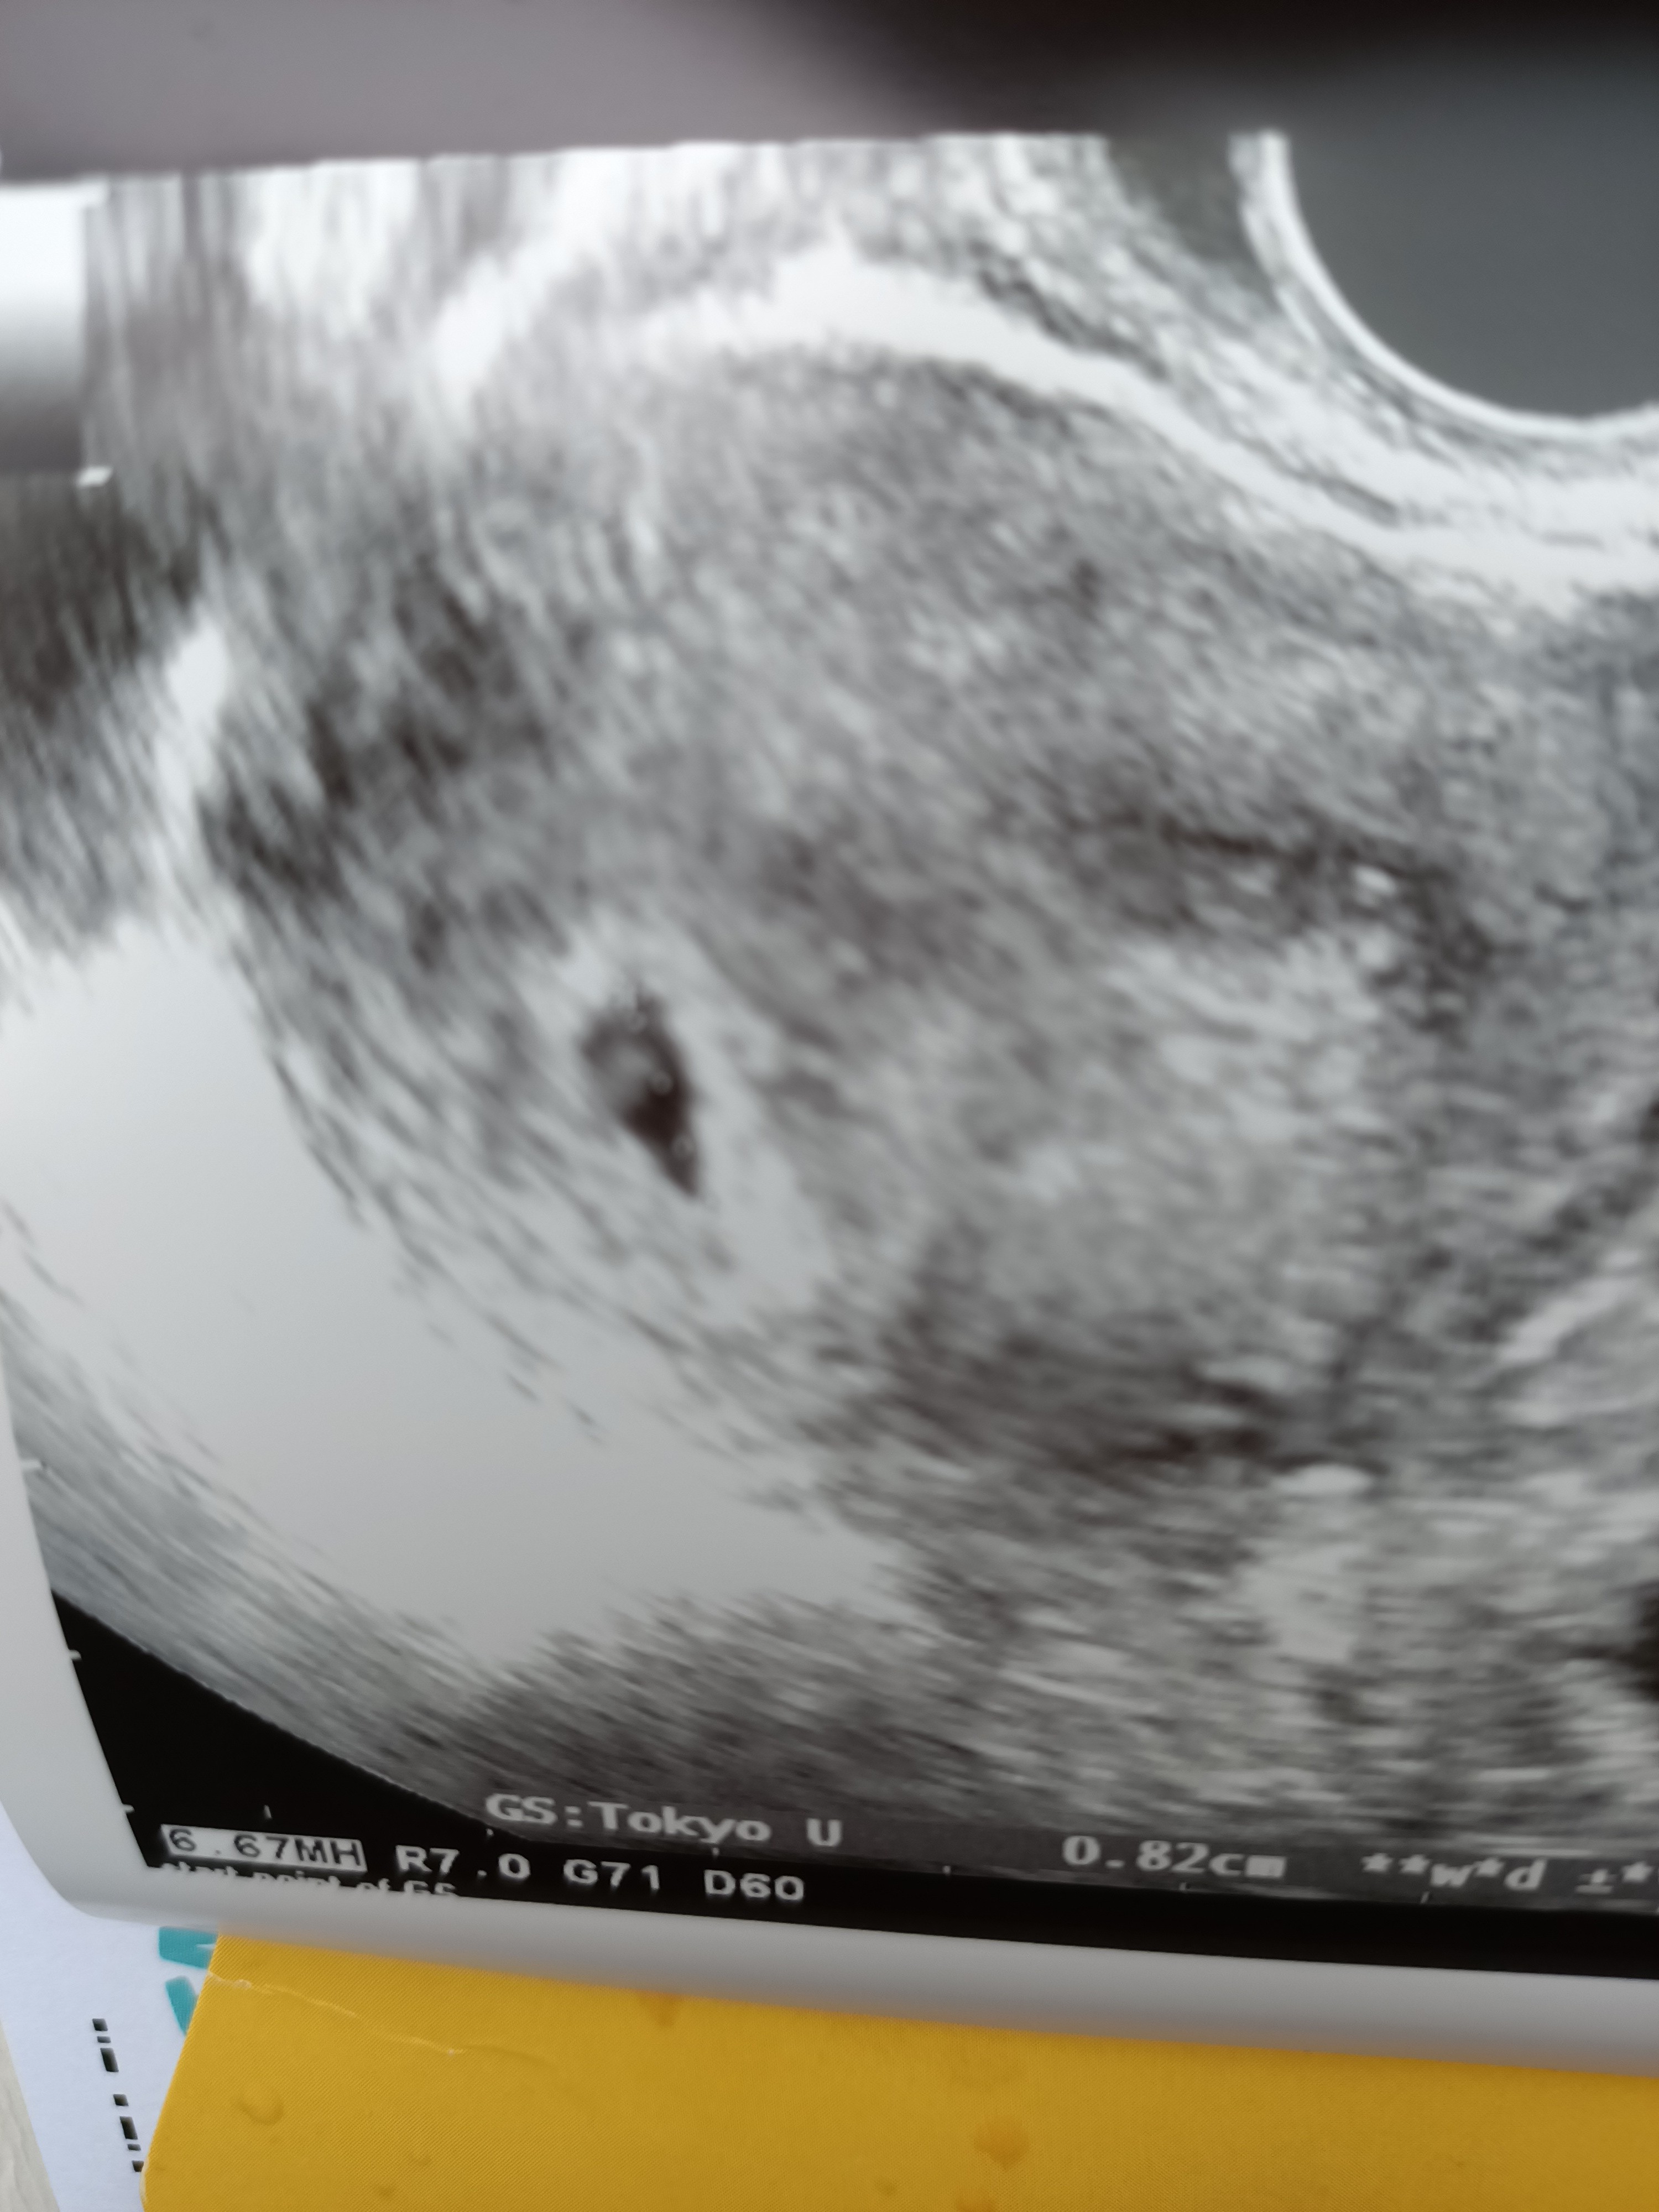

Jestem po wizycie 😀 6+3 tc. Ginekolog mówi że możliwe że jest serduszko ale jeszcze do końca nie widać. Mam pytanie do mam które dostały już skierowanie na badania laboratoryjne, oczywiście u lekarza na nfz. Czy macie wszystkie badania na NFZ ?

Załączniki

• IMG_20201222_122242.jpg

IMG_20201222_122242.jpg

1,3 MB · Wyświetleń: 118